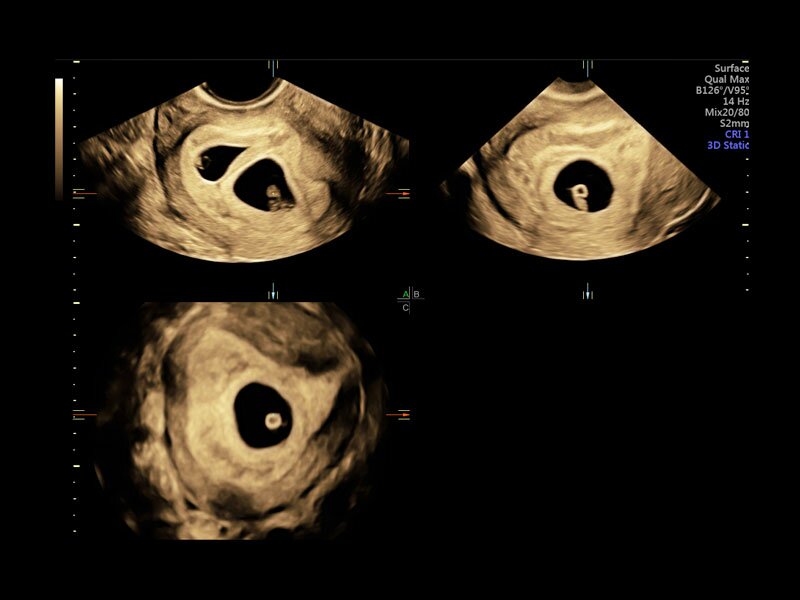

Клинические изображения

• Томографический ультразвук (TUI)

• Объемное контрастирование прямой плоскости - Basic VCI (VCI-A + VCI static)

• Advanced VCI (Volume Contrast Imaging) - расширенный программный пакет объемного контрастного изображения (VCI) для механических и электронных объемных датчиков:

• Проведение любой произвольной плоскости в 3D/4D (OmniView)

• Объемное контрастирование любой произвольной плоскости (OmniView+VCI)

• Регулировка толщины и формы коронарного среза в 3D/4D (получение коронарной плоскости в 3D/4D, например, для оценки мозолистого тела - автоматическая функция "Corpus Callosum"

• VOLUME CALCULATION II (VOCAL, Virtual Organ Computer Aided Analysis) – программное обеспечение для полуавтоматического определения контуров структур и расчета их объема в режиме объемной реконструкции для механических и электронных объемных датчиков

• SonoAVC (Sonography based Automated volume Count аnalysis) - программа для автоматического расчета размеров и объема анэхогенных образований/структур в режиме объемной реконструкции. Включает программу для расчета фолликулов и программу для расчета других анэхогенных структур для механических и электронных объемных датчиков